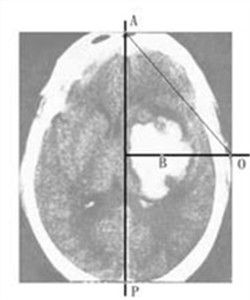

占位病變良性占位性病變從大體上可分為囊性占位和實質性占位兩種類型,囊性占位性病變主要包括囊腫、膿腫等,其中囊腫較常見;實質性占位主要包括血管瘤、細胞腺瘤、局灶性結節性增生、局灶性脂肪肝、炎性假瘤、瘤樣增生等,其中以血管瘤最為常見。發現有占位病變後,首先要定性論斷,即確定病人占位的性質,是良性還是惡性。各種影像學檢查不但可以配合定性論斷,還可以進行定位論斷,也就是進一步確定占位病變的位置、大小、數目及其與周圍組織的關係,定位診斷最常用的是CT、核磁共振掃描成像、B超,必要時可套用動脈血管造影,為能否手術治療提供依據。